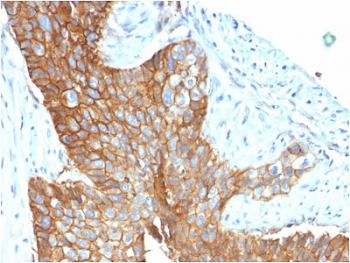

CD63 Antibody / LAMP-3 [orb2637613]

FACS, IF, IHC-P, WB

Human, Mouse

Mouse

Monoclonal

Unconjugated

100 μg